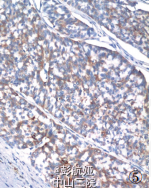

患者,62 岁,因发现右乳肿物 1 年,腹痛、腹胀 20 天伴血便入院。 查体:乳腺右侧外上象限触及一直径约 4 cm 肿物,质硬,活动,与周围界较清;左侧盆腔包块,直径约 11 cm。影像学检查:钼靶显示右乳腺浅分叶状高密度影,边界尚清,无钙化及毛刺征;CT 平扫盆腔类圆形实性肿块影,边界清晰,瘤体内见不定形钙化,结肠部分肠腔狭窄,肠壁增厚;遂行结肠镜检查示乙状结肠可见肿物,覆脓苔,质脆。 血清中 CEA 70. 23μg/ ml、CA125 422.15 KU/ L,CA199 137.53 U/ml。 遂行右乳肿物切除术 + 乙状结肠癌切除术及左侧附件切除术。 术中所见:右乳肿物分叶状,与周围界清;乙状结肠肿物与周围无粘连;左侧卵巢肿物包膜完整,未见腹水。 术后病理显示右乳腺内分泌癌,乙状结肠腺癌,左侧卵巢 Brenner 瘤。病理检查摇 眼观:右乳肿物 1 个,大小 3.5 cm *3 cm *2cm,无明确包膜,分叶状,切面灰白,质脆;结肠见一溃疡性肿物,大小 3. 5 cm *3 cm *1. 5 cm,切面灰白色,质脆,侵及全层;左侧卵巢肿物 1 个,大小 8 cm *6.5 cm*5 cm,包膜完整,切面淡黄色,质韧。 镜检:乳腺肿瘤由密集排列的细胞巢 组成,被纤细的纤维血管间质分隔,部分细胞呈短梭形,部分呈浆细胞样,可见菊形团结构(图 1);(结肠)肠壁间及浆膜下脂肪组织可见大部分癌组织排列成腺腔样,小部分呈片状分布,细胞核深染,异型明显,间质纤维化明显(图 2);卵巢肿瘤纤维瘤样间质中见巢状、岛状的移行细胞,瘤细胞呈咖 啡豆样,有纵行核沟,胞质丰富,嗜酸性,部分细胞巢中央有空腔(图 3)。 免疫表型:乳腺肿瘤 CgA(图 4)、NSE、CK、ER和 PR 均( + ),60% 细胞 Syn(图 5)( + ),HerbB-2、CA125 均( - );卵巢肿瘤 CK7、CK5/6 均( + ),Ki-67( - )。病理诊断:右乳神经内分泌癌;结肠腺癌;左侧卵巢Brenner 瘤。